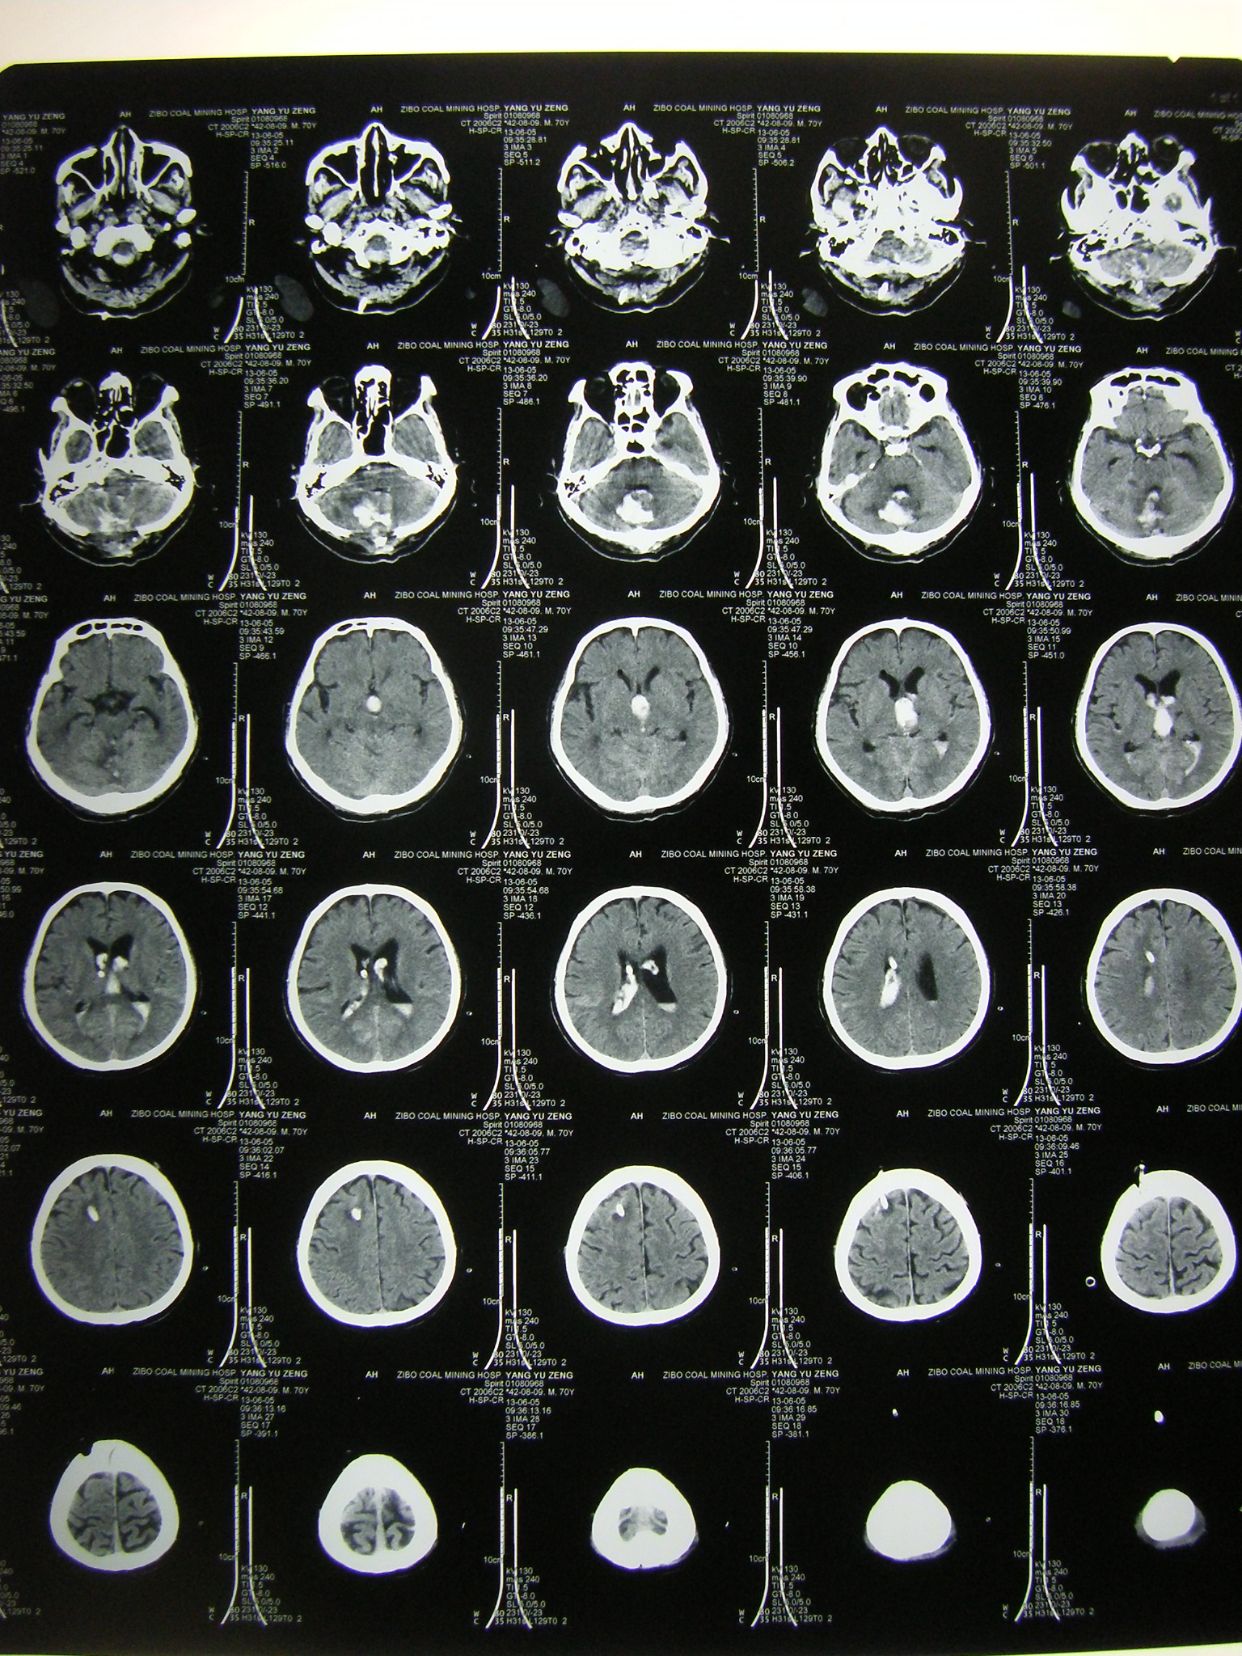

例2,患者女,54岁,突发头痛并意识不清3小时入院,有高血压、冠心病史多年,深昏迷,入院时出现呼吸停止,行气管插管,机械辅助呼吸。

CT示,小脑大量出血破入全脑室并梗阻性脑积水,与家属沟通并签字后急症行脑室外引流术,后颅凹开颅血肿清除术。

术后1天CT复查示,血肿清除满意,基底池可见,患者刺激睁眼。

患者术后1月,神志清,正确回答问题,四肢话动良好,出院康复。